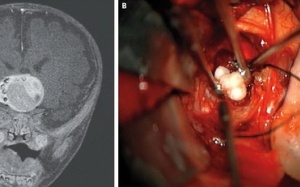

Các bác sĩ tại Trung tâm Y tế ĐH Maryland, Mỹ đã giải phẫu lấy khối u có răng trong não một bé trai 4 tháng tuổi.